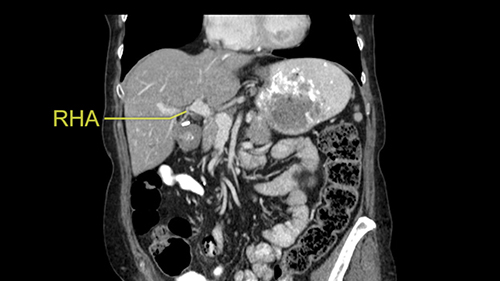

So I would then focus on the hepatic outflow because that’s the way we do the operation is by mobilizing the liver. So the vena cava looks quite normal. The right hepatic vein looks quite normal. There are no large additional outflow veins from the right lobe which would generate slowing down moments. The hepatic artery is unremarkable and is not usually an issue we can define the anatomy quite clearly at surgery.

![[RHA]](jpg/preop_sg_moment3.jpg)